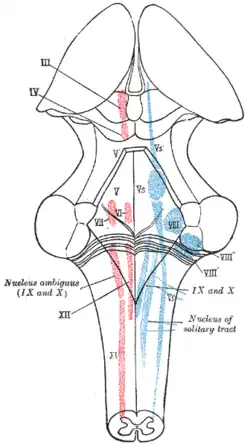

Diagram of brain stem showing the nuclei of the cranial nerves | |

The cranial nerve nuclei schematically represented; dorsal view. Motor nuclei in red; sensory in blue.

The cranial nerve nuclei schematically represented; dorsal view. Motor nuclei in red; sensory in blue. Nuclei of origin of cranial motor nerves schematically represented; lateral view.